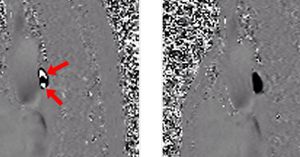

VENC stands for velocity encoding, a parameter that must be specified before performing a phase-contrast (PC) MRI or MRA study. VENC, measured in cm/sec, should be chosen to encompass the highest velocities likely to be encountered within the vessel of interest. If VENC is set to 50 cm/sec, for example, flows in the range of ±50 cm/sec can be accurately represented by a set of phase shifts spanning from −180° to +180°. If VENC is picked too low, velocity aliasing may occur with faster flows not being appropriately represented. Fig (left) PC study of pulmonary artery with VENC set too low (15 cm/sec). Note velocity aliasing (white areas) which appears to be flow in the wrong direction. (right) PC study of pulmonary artery with VENC set properly (30 cm/sec). The vessel is properly displayed as black with velocity aliasing no longer apparent.